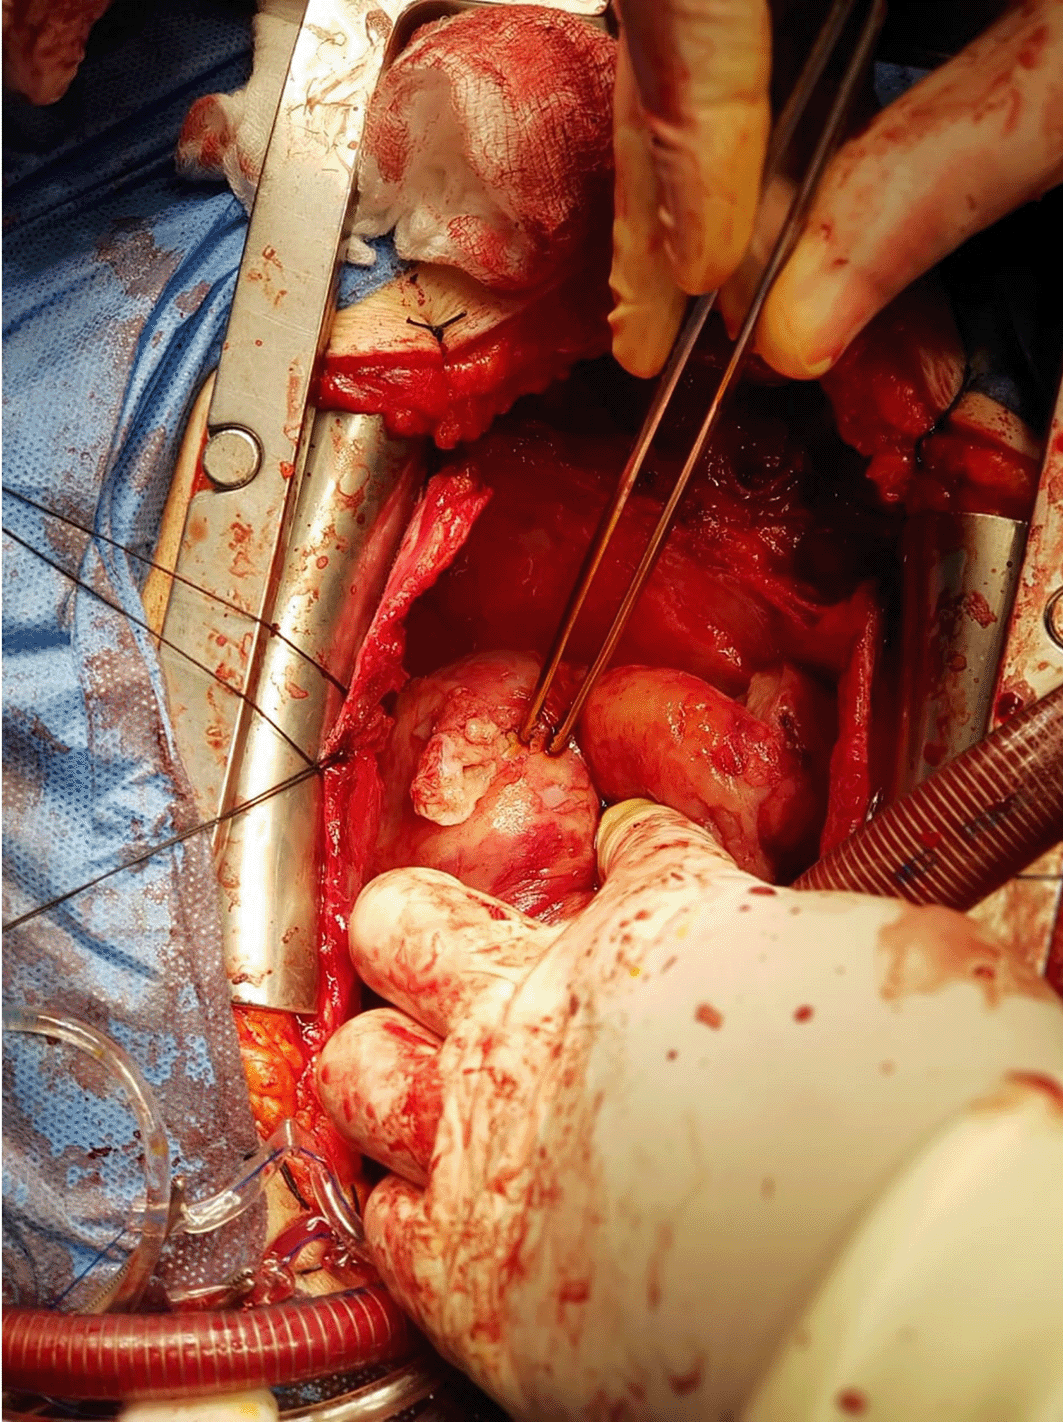

Three patients had ruptured hydatid cysts, two patients had intrapericadial rupture with pericardial adhesion, and one patient had a ruptured cyst in the left atrium (intracardiac ruptured), while the last two patients had intact hydatid cysts, as shown in Figures 3, 4 and 5.

9ce42333-239b-48ec-8ad7-95a2bf74850e_figure3.gif

Figure 3. Intact left ventricular hydatid cyst with needle for aspiration of cysts content.